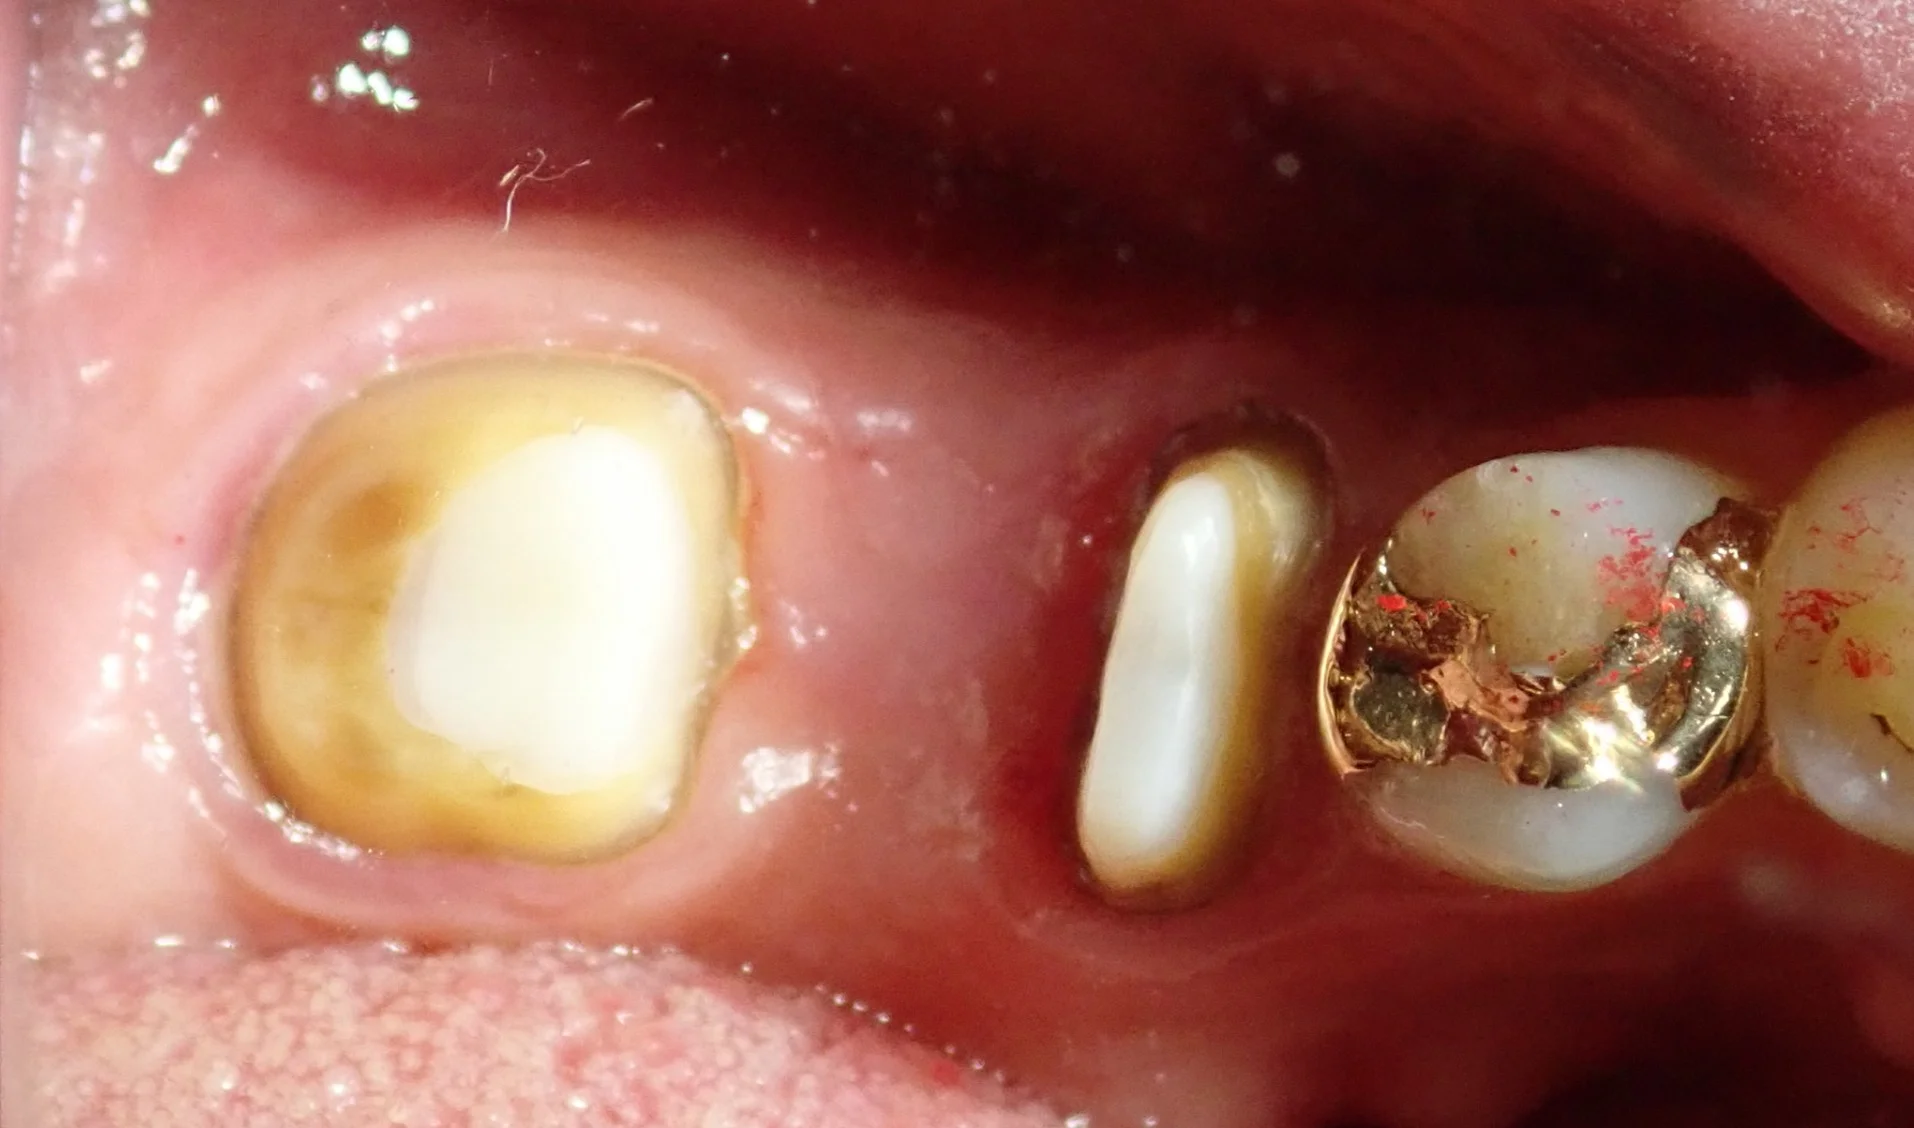

こちらの方は私が治療に入った時にはファイバーコアが入っていましたが・・・

その前は太いメタルコアが入れられていたそうです。

実際に被せ物を除去して根の状態を直接肉眼で確認したところ、後ろ側の根がレントゲンには写らないラインで真っ二つに折れていました。

通常、歯根破折が起こった歯の第一選択は「抜歯」になります。

ただし、ここで待っていただきたいのが・・・

写真のような根が2つある歯についてです。

折れているのがどちらか一方であれば、もう一方はまだ温存できる状態になります。

なので、こんな感じで一本だけ抜歯すれば、手前の根は残すことが出来るようになります。

実際のお口の中の写真がこちらです。